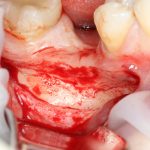

Кстати, обрати внимание на ширину альвеолярного гребня (левая картинка). Она чуть меньше 3 мм. Это объясняет, почему я засомневался в возможности установки имплантатов одновременно с остеопластикой. Понятно и без КЛКТ.

Наперво, мне нужно удалить разрушенный зуб и получить костный аутотрансплантат.

Возвращаемся к основной операционной области. Еще раз посмотрим на альвеолярный гребень, поофигеваем от его ширины и моих грандиозных планов: